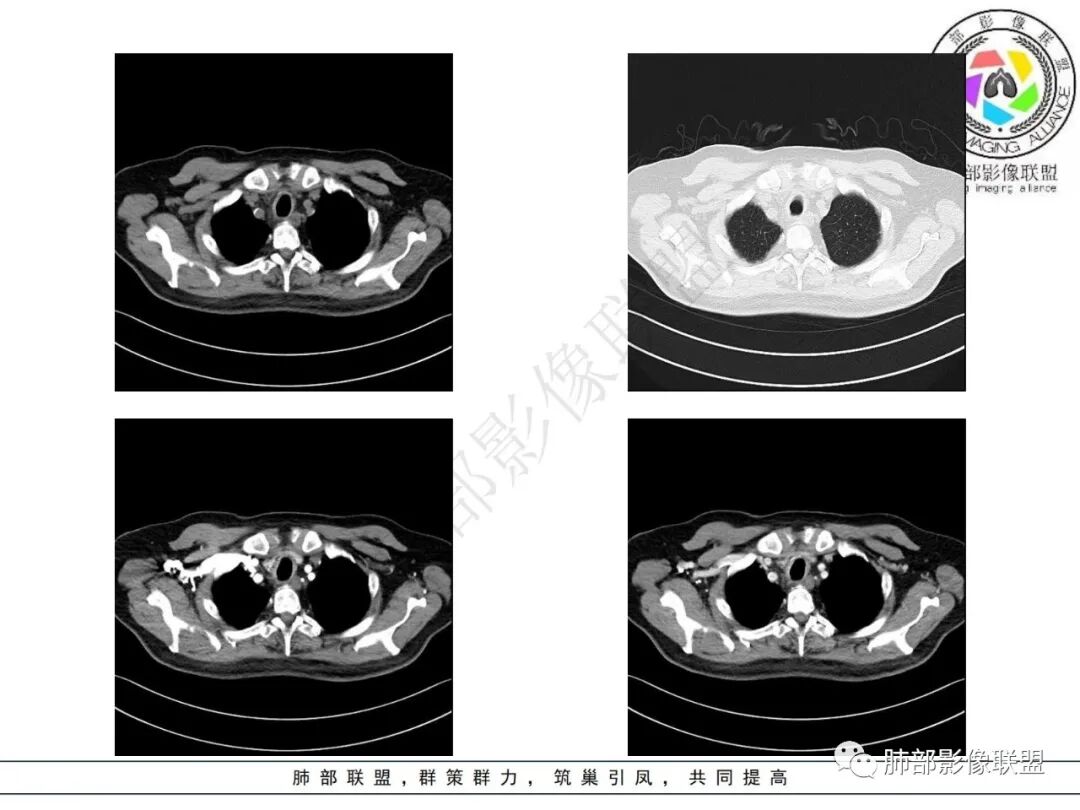

2.影像表现:双肺上叶见结节影及条索影,树丫等,边界可分辨。气管支气管壁广泛增厚、钙化,形态相对均匀一致,上达声门区。支气管膜部受累。增强轻中度强化。纵隔见轻度增大淋巴结。

3.综合分析:双肺上叶病灶较符合继发性肺结核。支气管病变分布具有广泛性、一致性。支气管壁广泛增厚钙化常见于淀粉样变性。累及膜部气管支气管病变的有淀粉样变性和GPA

老年男性,气管入口至右主支气管壁弥漫性增厚,累及膜部,未见结节状凸起,考虑气管支气管淀粉样变性,鉴别复发性多软骨炎(不累及膜部),弥漫肉芽肿多血管炎(结节状增厚)。

老年男性,气管全层受累(膜部受累),累及气管、主支气管,纵隔、肺门区无肿大淋巴结,首先考虑淀粉样变性,没有结节感,不考虑TO,复发软骨炎不累及膜部

患者,男,73,间断咳嗽半年,加重半月。双肺底细湿啰音,双下肢轻度水肿。糖尿病、糖尿病微血管病变、慢性肾病、高血压、冠心病、陈旧心梗、冠脉支架、脑梗、慢性胃病史,得全了。吸烟史。血像、ESR增高。胸部CT:气管壁弥漫全层增厚,膜部也受累,气管腔外形仍在、无缩窄,病变延及左右主支气管,纵隔可见肿大淋巴结,大血管壁多发钙化,双肺上叶可见多发树芽,两侧胸膜局限性增厚。考虑:TB?淀粉样变?鉴别GPA、复发性多软骨炎、气管支气管骨化、转移性钙化等。